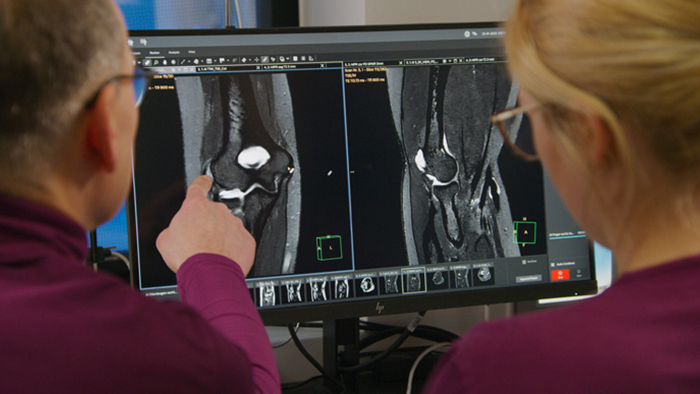

Dr. Katahira and technologist reviewing images on MR console

At Kumamoto Chuo Hospital, Japan, Dr. Kazuhiro Katahira has been achieving fast, high quality images with AI-enabled SmartSpeed MRI technology. In use for six months, he describes the image quality improvements that he has seen in imaging of the whole body, spine, abdomen, prostate, breast and more. He also highlights the great impact of motion-free imaging in upper abdominal and prostate exams.